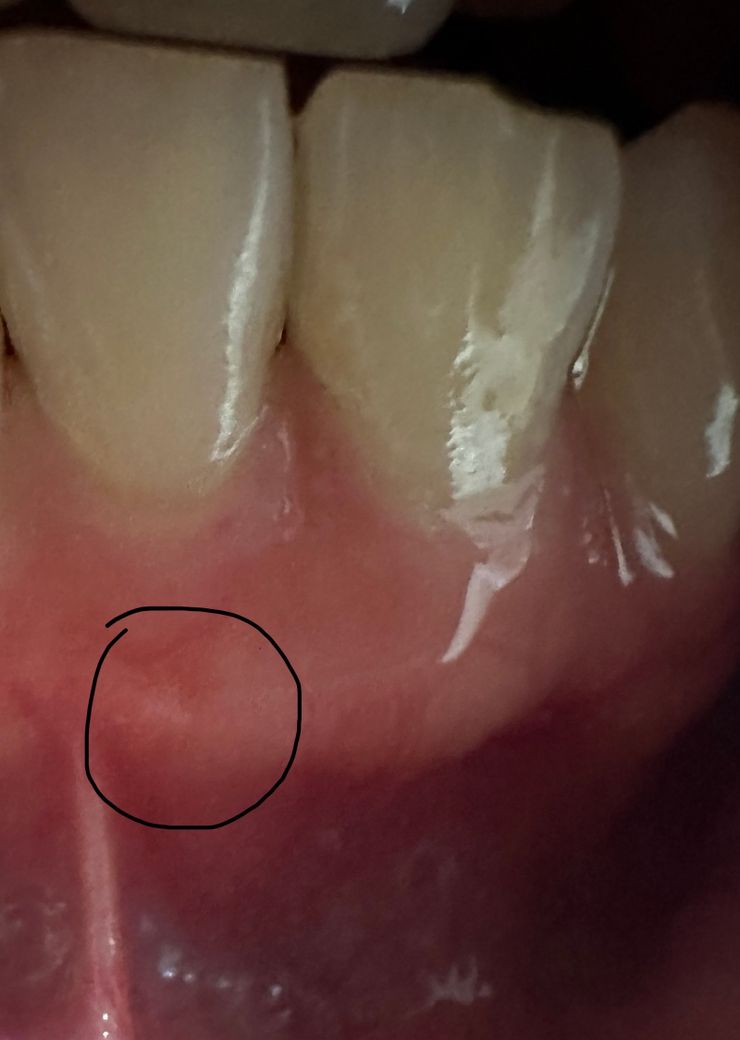

아랫니 잇몸에 뭐가 났는데 약간 시려요 염증인가요?

오늘 점심부터 아랫니가 약간 시려서 보니까 시린니 잇몸에 뭐가 구내염처럼 난거 같은데 조그마한 하얀 뾰루지 같은게 있는거 같아요ㅠㅠ 염증일까요? 그 치아가 가만히 있어도 약간 시큰시큰 해요

사진으로는 정확한 확인이 어려워 보입니다 치약 뿌리 끝에 염증이 있다면 뾰루지 같은 모양이 나올 수도 있습니다 자세한 확인을 위해서 치과에서 진료를 받아 보는 것을 권유 드립니다

사진 하나로 판별하기는 어렵습니다. 구내염이면 1주일 정도면 사라질것이니 안사라지면 치과 가보시면 됩니다.

염증은 아닌거 같고 상처가 생긴거 같습니다. 일단은 최대한 저부위에 자극이 가지 않도록 해주시는게 좋을것같습니다.

정확한 것은 x-ray 및 임상검사를 해보아야 합니다. 지금 사진만으로는 이것이 염증인지, 구내염인지 아니면 단순히 잇몸 에 비춰보이는 치조골인지 알 수 없습니다. 따라서 정확한 판단을 위해서는 치과 방문을 권해드립니다.

해당부위 잇몸에 염증이 생긴 것으로 보이며, 이경우 치과에 방문하여 상태 확인후 스케일링이나 잇몸치료와 같은 적절한 치료를 받길 권합니다.

잇몸염증의 경우 치아가 원인일 수도 있고 잇몸이 원인일수도 있습니다 만약 치아 속 신경에서 비롯된 염증이라면 신경치료가 필요할 수 있겠습니다